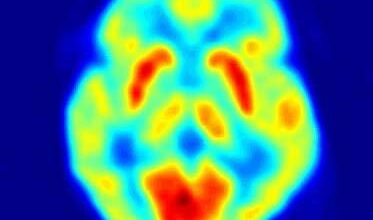

باستخدام أحدث تكنولوجيا التصوير بالرنين المغنطيسي المتطورة المتوفرة في CNIC ، تمكن فريق البحث من دراسة مجموعة من المعلمات على أساس أسبوعي ، وبالتالي تحديد مؤشرات الضرر في وقت أبكر بكثير من التغييرات في أي من العلامات المستخدمة في السريرية الحالية ممارسة. وأوضح العالم فيليبس الدكتور خافيير سانشيز غونزاليز ، القائد المشترك للدراسة ، أنه بهذه الطريقة ، "وجدنا أن المعلمة الأولى لإظهار أي تغيير هي رسم الخرائط T2 ، مما يدل على وجود ذمة – تراكم المياه ، وتم تأكيد هذه النتيجة في وقت لاحق من خلال الدراسات النسيجية ".

ال JACC تؤكد الدراسة أن رسم الخرائط T2 يتغير في وقت مبكر عن أي معلمة أخرى معروفة في الاستخدام الحالي ، تحدث حتى قبل أي تعديلات محلية أو إقليمية لانقباض القلب. إن توفر مثل هذه العلامة المبكرة لأمراض القلب يمكن أن يساعد الأطباء في تحديد المرضى الذين يتحملون علاج أنثراسيكلين حتى عند تناول جرعات عالية. وكما أوضح الدكتور إيبانيز ، في هذه المجموعة من المرضى ، "يمكن علاج تكرار الإصابة بالسرطان باستخدام anthracyclines عند الجرعات العالية الأكثر فاعلية." في المرضى الآخرين ، "إن تطوير هذه العلامة عند جرعة أنثراسيكلين تراكمية منخفضة يمكن أن يكون مؤشرا للعلاج الوقائي لأمراض القلب أو تعديل لنظام العلاج الكيميائي."